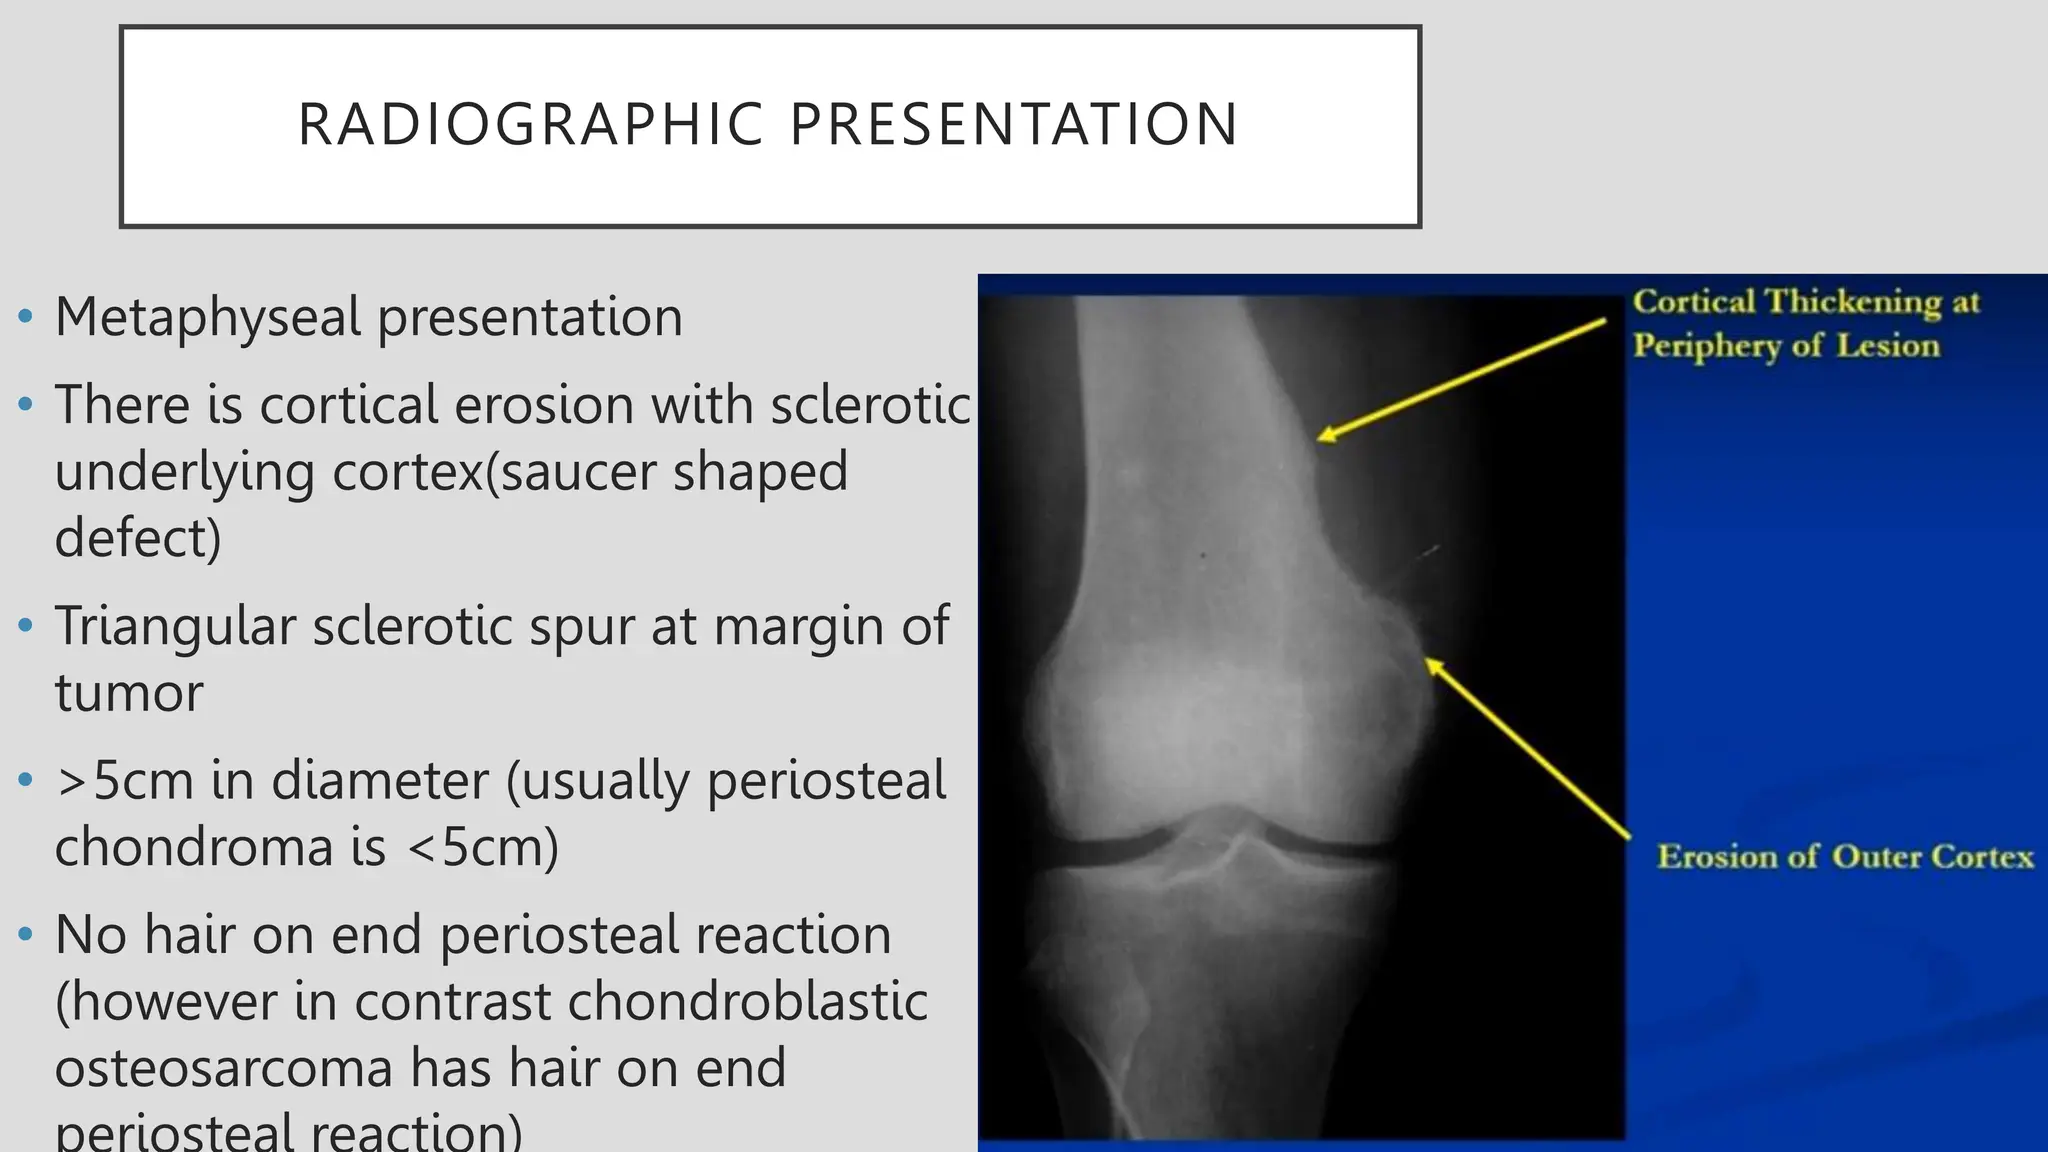

RADIOGRAPHIC PRESENTATION

• Metaphyseal presentation

• There is cortical erosion with sclerotic

underlying cortex(saucer shaped

defect)

• Triangular sclerotic spur at margin of

tumor

• >5cm in diameter (usually periosteal

chondroma is <5cm)

• No hair on end periosteal reaction

(however in contrast chondroblastic

osteosarcoma has hair on end

RADIOGRAPHIC PRESENTATION • Metaphysealpresentation • There is cortical erosion with sclerotic underlying cortex(saucer shaped defect) • Triangular sclerotic spur at margin of tumor • >5cm in diameter (usually periosteal chondroma is <5cm) • No hair on end periosteal reaction (however in contrast chondroblastic osteosarcoma has hair on end